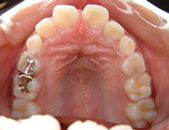

2か月後です。反対咬合は治っています。現在は正常な噛み合せになりました。

これからまだ永久歯に生え替わるので、注意深く定期的に観察していきます。生え替わった後に、また反対咬合になりこともあります。